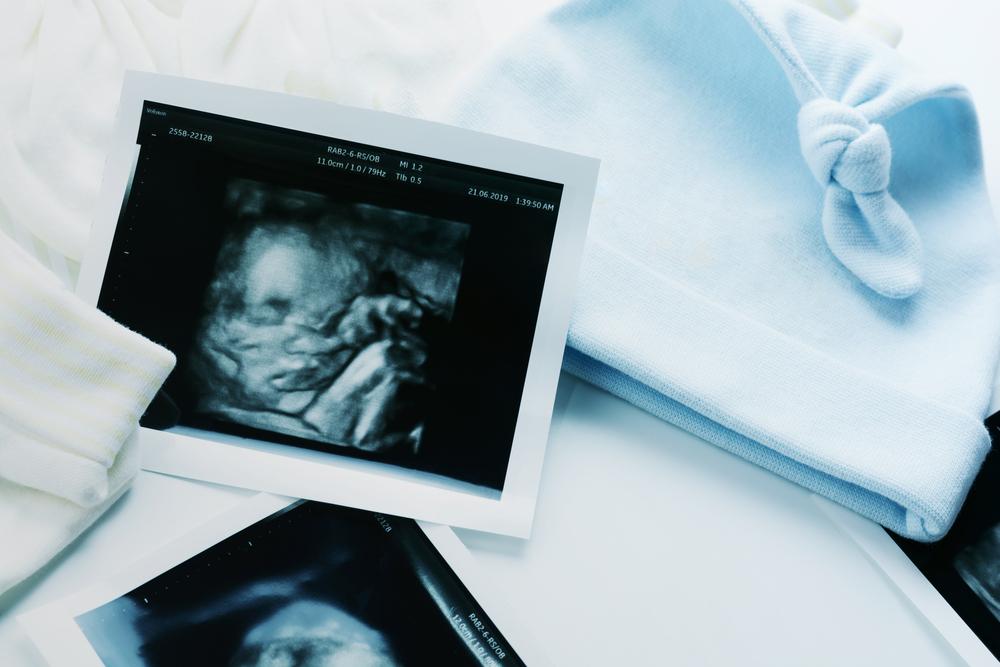

Nhiều mẹ bầu thường thắc mắc siêu âm hình thái học là gì? Siêu âm hình thái học là kỹ thuật siêu âm cho phép quan sát hình ảnh của thai nhi trong bụng mẹ. Quá trình quét có thể kiểm tra được kích thước thai nhi, hình dáng bên ngoài lẫn các cơ quan bên trong cơ thể của em bé, đồng thời góp phần phát hiện một số dị tật (nếu có).

Kỹ thuật siêu âm này có thể được thực hiện bất cứ lúc nào trong khoảng từ tuần 18 đến 22 của thai kỳ nhưng lý tưởng nhất là khi thai được 20 tuần. Nguyên nhân là vì ở giai đoạn này, thai nhi đã phát triển và hoàn thiện các cơ quan bên ngoài lẫn bên trong cơ thể nên rất dễ quan sát khi quét siêu âm.

Vậy siêu âm hình thái học có phải là siêu âm 4d không? Thực tế là hiện nay các bác sĩ thường thực hiện siêu âm bằng các máy siêu âm 3D, 4D. Mẹ bầu có thể tiếp tục thực hiện phương pháp siêu âm này nhiều lần trong thai kỳ tùy theo mong muốn hoặc chỉ định của bác sĩ.